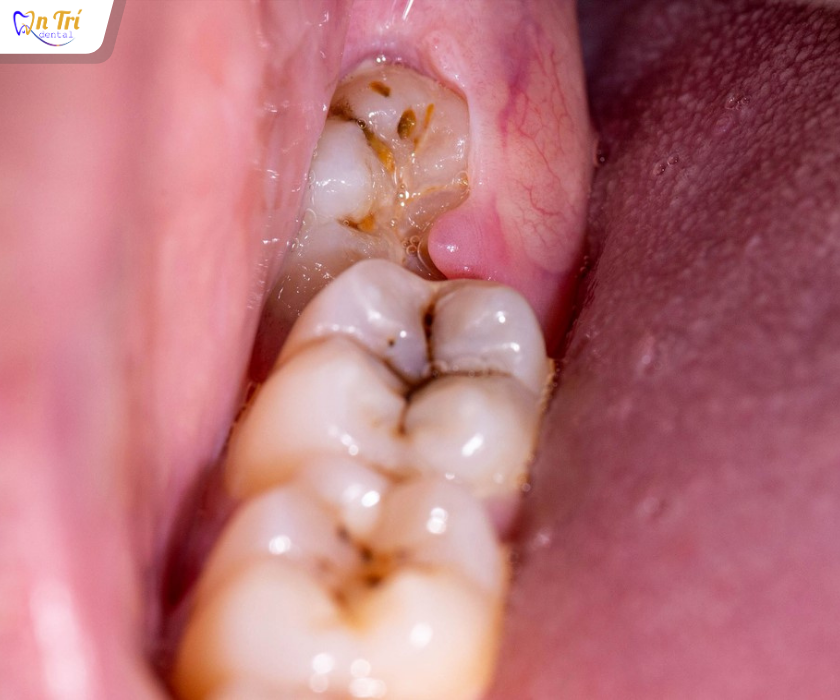

2. Viêm lợi và nhiễm trùng nướu

Răng khôn nằm sâu khiến việc vệ sinh khó khăn, tạo môi trường cho vi khuẩn tích tụ. Hậu quả là viêm lợi, sưng tấy, đau nhức, hôi miệng và đôi khi là nhiễm trùng lan rộng. Những biến chứng này có thể ảnh hưởng đến các khu vực xung quanh như má, tai hoặc nặng hơn là dây thần kinh, gây nguy hiểm đến tính mạng.